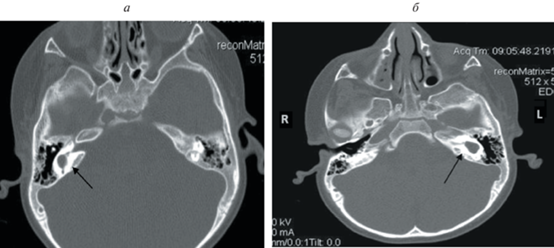

Компьютерная томография височных костей (рис. 1, а, б) выявила рудиментарно измененные улитки с обеих сторон, полукружные каналы дифференцировались неотчетливо и сливались с расширенным преддверием – внутренне ухо с обеих сторон было представлено единой полостью неправильной формы размерами справа 10.3 × 7.2 мм, слева – 12.6 × 6.9 мм.

Рис. 1.

Компьютерная томография ребенка Т. Аномалия внутреннего уха – общая полость (а – справа, б – слева).

Цепи слуховых косточек не были нарушены. Внутренний слуховой проход диаметром справа 1.4–2.7 мм, слева – 3.3 мм.